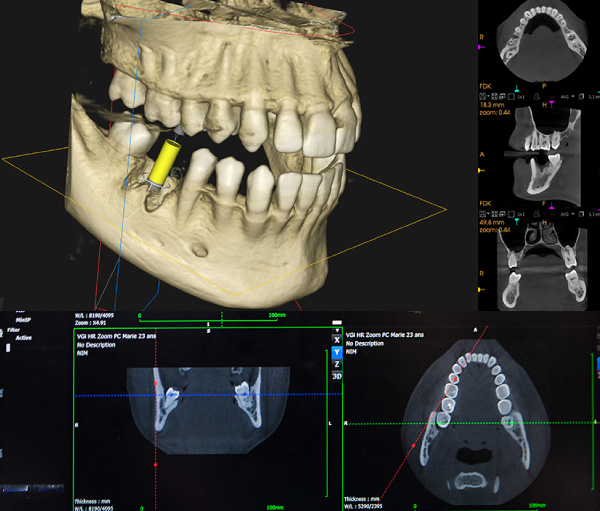

時代とともにDX(デジタルトランスフォーメーション)と、IT化が進み、デンタルクリニックも治療のデジタル化が進んでいます。一人ひとりの口腔内を3Dシミュレーションで予見を行い、難症例における精密治療を可能にしています。

インプラント外科による骨、神経、血管の検査や、歯の内部から治療する根管治療まで、精密な治療が実現できました。

歯科用CT

モニターシステム、CAD/CAM、3Dシミュレーションなどを活用し、診療を体系化したデジタル環境。歯科用CT、セファロなど口腔外科・審美矯正に対応した安全な治療を実現できます。